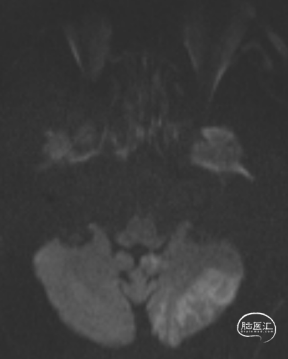

术后头晕呕吐,当日DWI:左侧小脑梗死,MRA未见明显大血管栓塞。

术后第3天患者恶心、呕吐症状消失,仍有头晕,复查DWI及MRA。

术后第5天,头晕症状完全消失,双上肢收缩压差8mmHg,NIHSS 0分。